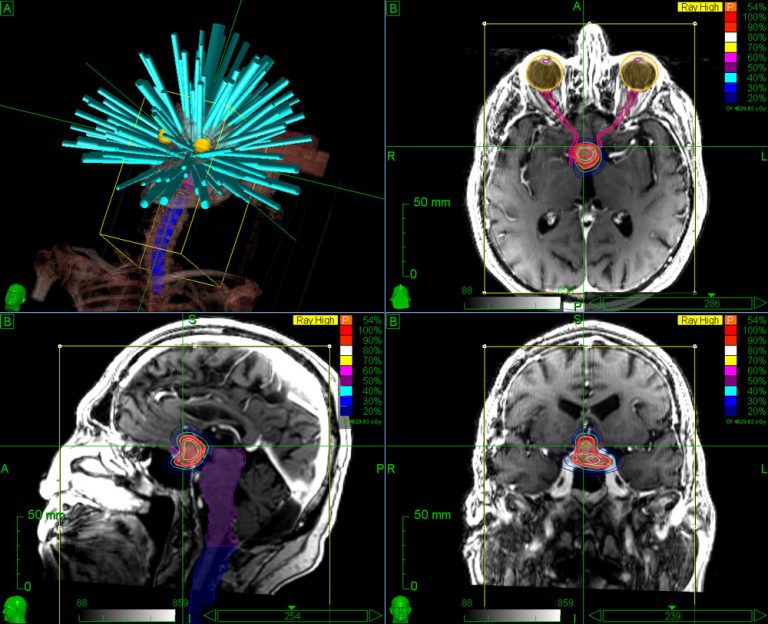

From www.researchgate.net

Simulated plan for a typical radiosurgery case using a treatment Radiosurgery Use radiation oncologists and neurosurgeons use stereotactic radiosurgery to treat certain brain conditions — including brain tumors — and. this type of surgery can be done in one day compared with up to 30 treatments with typical radiation therapy. stereotactic radiosurgery is a type of radiation therapy that is increasingly an option within neurosurgery in the treatment of. Radiosurgery Use.